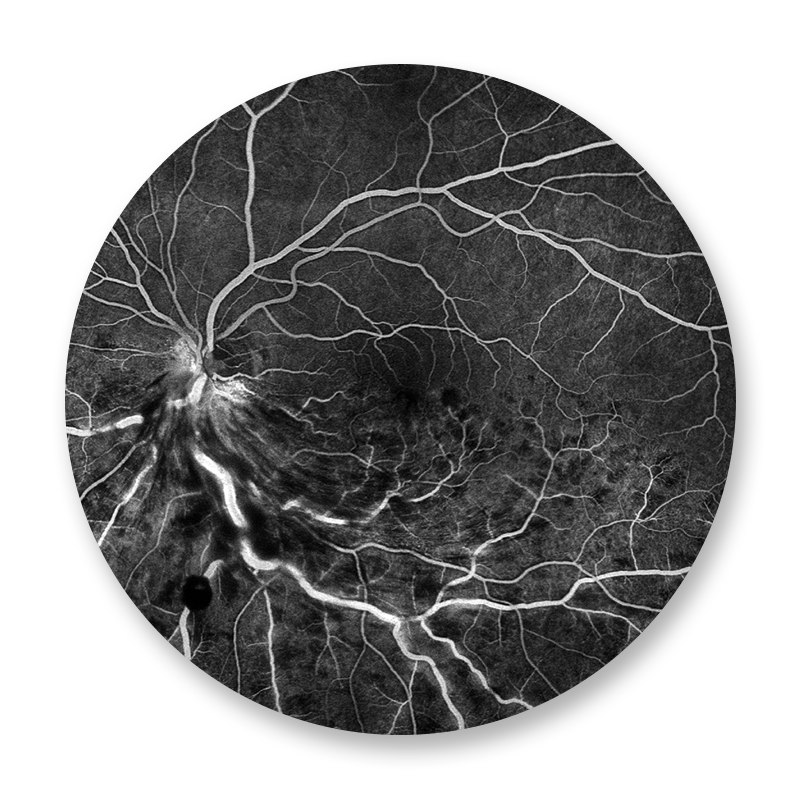

Der Augenhintergrund wird mit einer aufwendigen digitalen Kameratechnik fotografiert. Während der FAG wird zuerst eine Farbaufnahme und eine Autofluoreszenzaufnahme des Augenhintergrundes erstellt. Es folgt die intravenöse Gabe eines Farbstoffes, der sich in den Gefäßen der Netzhaut darstellt und dort krankhafte Veränderungen anzeigt. Die Fluoreszenzangiographie spielt eine wichtige Rolle bei der Beurteilung und Therapieplanung der altersbedingten Makuladegeneration, bei Gefäßverschlüssen, so wie bei der diabetischen Netzhauterkrankung.

Unter dem Begriff Maculadegeneration wird eine Gruppe von Erkrankungen des Auges zusammengefasst, die die Macula lutea („der Punkt des schärfsten Sehens“) – auch „Gelber Fleck“ genannt – der Netzhaut betreffen und mit einem allmählichen Funktionsverlust der dort befindlichen Gewebe einhergehen. Die weitaus häufigste Form der Maculadegeneration ist die altersbedingte (oder senile) Maculadegeneration (AMD). Vor der Therapie muss zwischen der feuchten und der trockenen Form der Maculadegeneration unterschieden werden. Hauptrolle spielt hier die OCT Untersuchung und die Fluoreszenzangiographie. Die feuchte Form kann zu einem sehr schnellen Verlust der Sehkraft führen. Sie wird heute durch intravitreale operative Medikamentengaben (IVOM) von Anti-VEGF-Medikamenten (z. B. Avastin, Lucentis, Eylea) behandelt.